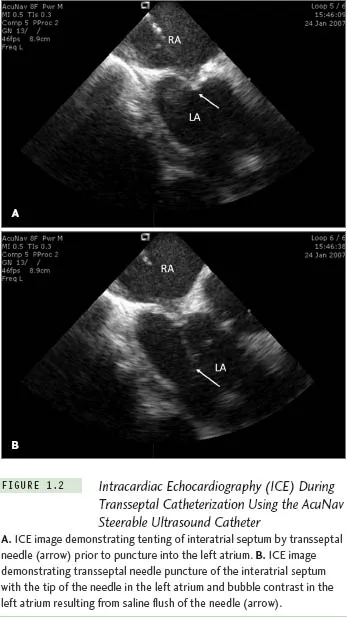

While the technique of transseptal catheterization remains largely unchanged since it was originally described and modified,14 several new technologies have made the approach considerably easier and potentially less risky, and are routinely employed today in many clinical electrophysiology laboratories. These new technologies include transesophageal echocardiography,33 now largely replaced by intracardiac echocardiography (ICE),34-37 to guide transseptal puncture, transseptal puncture performed using radio-frequency energy applied to a modified transseptal needle (NRG RF Transseptal Needle, Baylis Medical Company, Inc, Montreal QC, Canada), or use of a needle-tipped guidewire (SafeSept Transseptal Guidewire, Pressure Products, Inc, San Pedro, CA) passed through a standard Brockenbrough transseptal needle into the left atrium through a variety of pre-shaped transseptal sheaths (Fast-Cath, St. Jude Medical, Inc, St. Paul, MN). With the use of ICE, typically performed with a steer-able 8 F or 10 F intracardiac ultrasound catheter (AcuNav, Siemens Medical Solutions USA, Inc, Malvern, PA), contrast injection to stain the septum is no longer required, since micro-bubbles in the saline flush provide adequate echo-contrast to ensure successful left atrial access, reducing the risk of cardiac perforation with the transseptal needle (Figure 1.2). The radiofrequency transseptal needle38 and the needle-tipped guidewire further reduce the risk of inadvertent needle perforation of the left atrial lateral wall or roof during transseptal catheterization. For ablation of left-sided accessory pathways, a numbered series of transseptal sheaths (eg, SL1, SL2 [Daig Corp, Minnetonka, MN]) with different lengths of the distal-shaped segment was developed that, when extended just beyond the sheath, position the ablation catheter at specific locations around the mitral valve annulus (Fast-Cath, St. Jude Medical, Inc, St. Paul, MN).